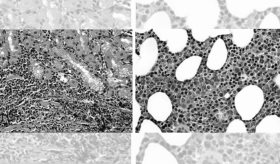

En términos generales, la leucemia es un tipo de cáncer que se origina en las células sanguíneas a nivel de la médula ósea, más comúnmente a partir de los glóbulos blancos. Inicia con el mal funcionamiento y transformación de unas cuántas células que, con el tiempo sobrepasan la población de células normales por su capacidad de crecimiento descontrolado. Adicionalmente, las células cancerosas no siguen el ciclo de vida de una célula sanguínea normal, por lo que no mueren en el momento debido y se acumulan en la médula ósea, trayendo como consecuencia la incapacidad de ésta para producir otro tipo de células. Es por esto que, los pacientes que sufren de leucemia pueden presentar dificultad para combatir las infecciones por falta de glóbulos blancos, para controlar un sangrado por falta de plaquetas o llevar oxígeno a los tejidos por falta de glóbulos rojos, dependiendo de cada caso. Así mismo, estas células cancerosas pueden posteriormente diseminarse hacia el torrente sanguíneo alcanzando otros órganos como el bazo o el hígado, alterando también el funcionamiento de éstos.

Ahora bien, según las características microscópicas y los signos y síntomas presentados por el paciente, las leucemias pueden clasificarse como agudas o crónicas. En el caso de las leucemias agudas, como su nombre lo dice, se manifiesta de forma aguda, es decir que en corto tiempo el paciente refiere síntomas como fatiga, fiebre, sangrados, dolor articular, entre otros, ya que las células se multiplican con mucha rapidez dando lugar a formas inmaduras, lo cual puede definirse gracias a sus características estructurales. Por otro lado, hablamos de una leucemia crónica cuando las células cancerosas han madurado parcialmente y en estructura, puede decirse que se asemejan más a una célula sanguínea normal, aunque no del todo, por lo que no ejercen adecuadamente su función. Adicionalmente, en cuanto al curso de la enfermedad, las leucemias crónicas suelen ser más lentas, por lo que los pacientes pueden vivir muchos años con la enfermedad sin notar ningún síntoma. No obstante, las leucemias crónicas suelen ser más retantes a la hora del tratamiento.

Por último, la clasificación histológica de cada una de las leucemias dependerá de su línea celular de origen dividiéndose en linfocítica o mieloide, que a su vez se distinguen entre sí por otros factores como edad de presentación, genes asociados, signos y síntomas característicos e incluso, pronóstico.